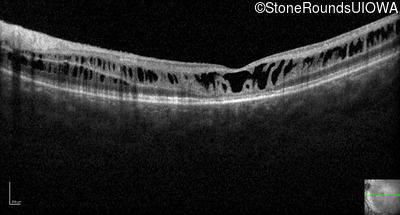

Optical Coherence Tomography - Left - 10/40

Exemplar / OCT Stack